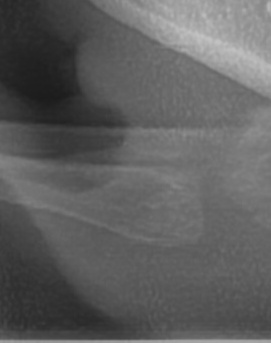

Previous image Next image